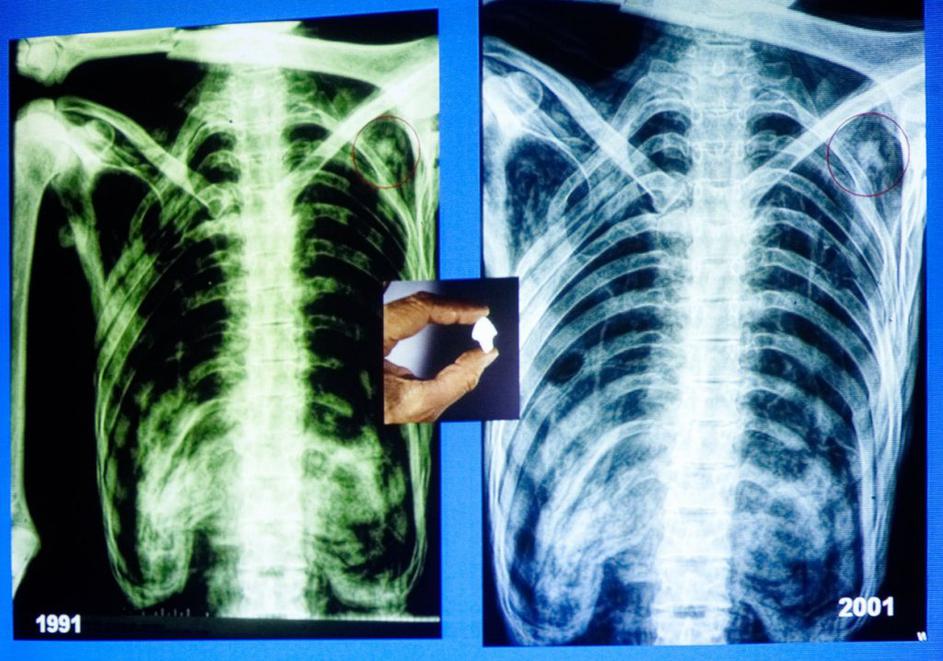

Ötzi Rentgen trupla Profimedia Ötzi